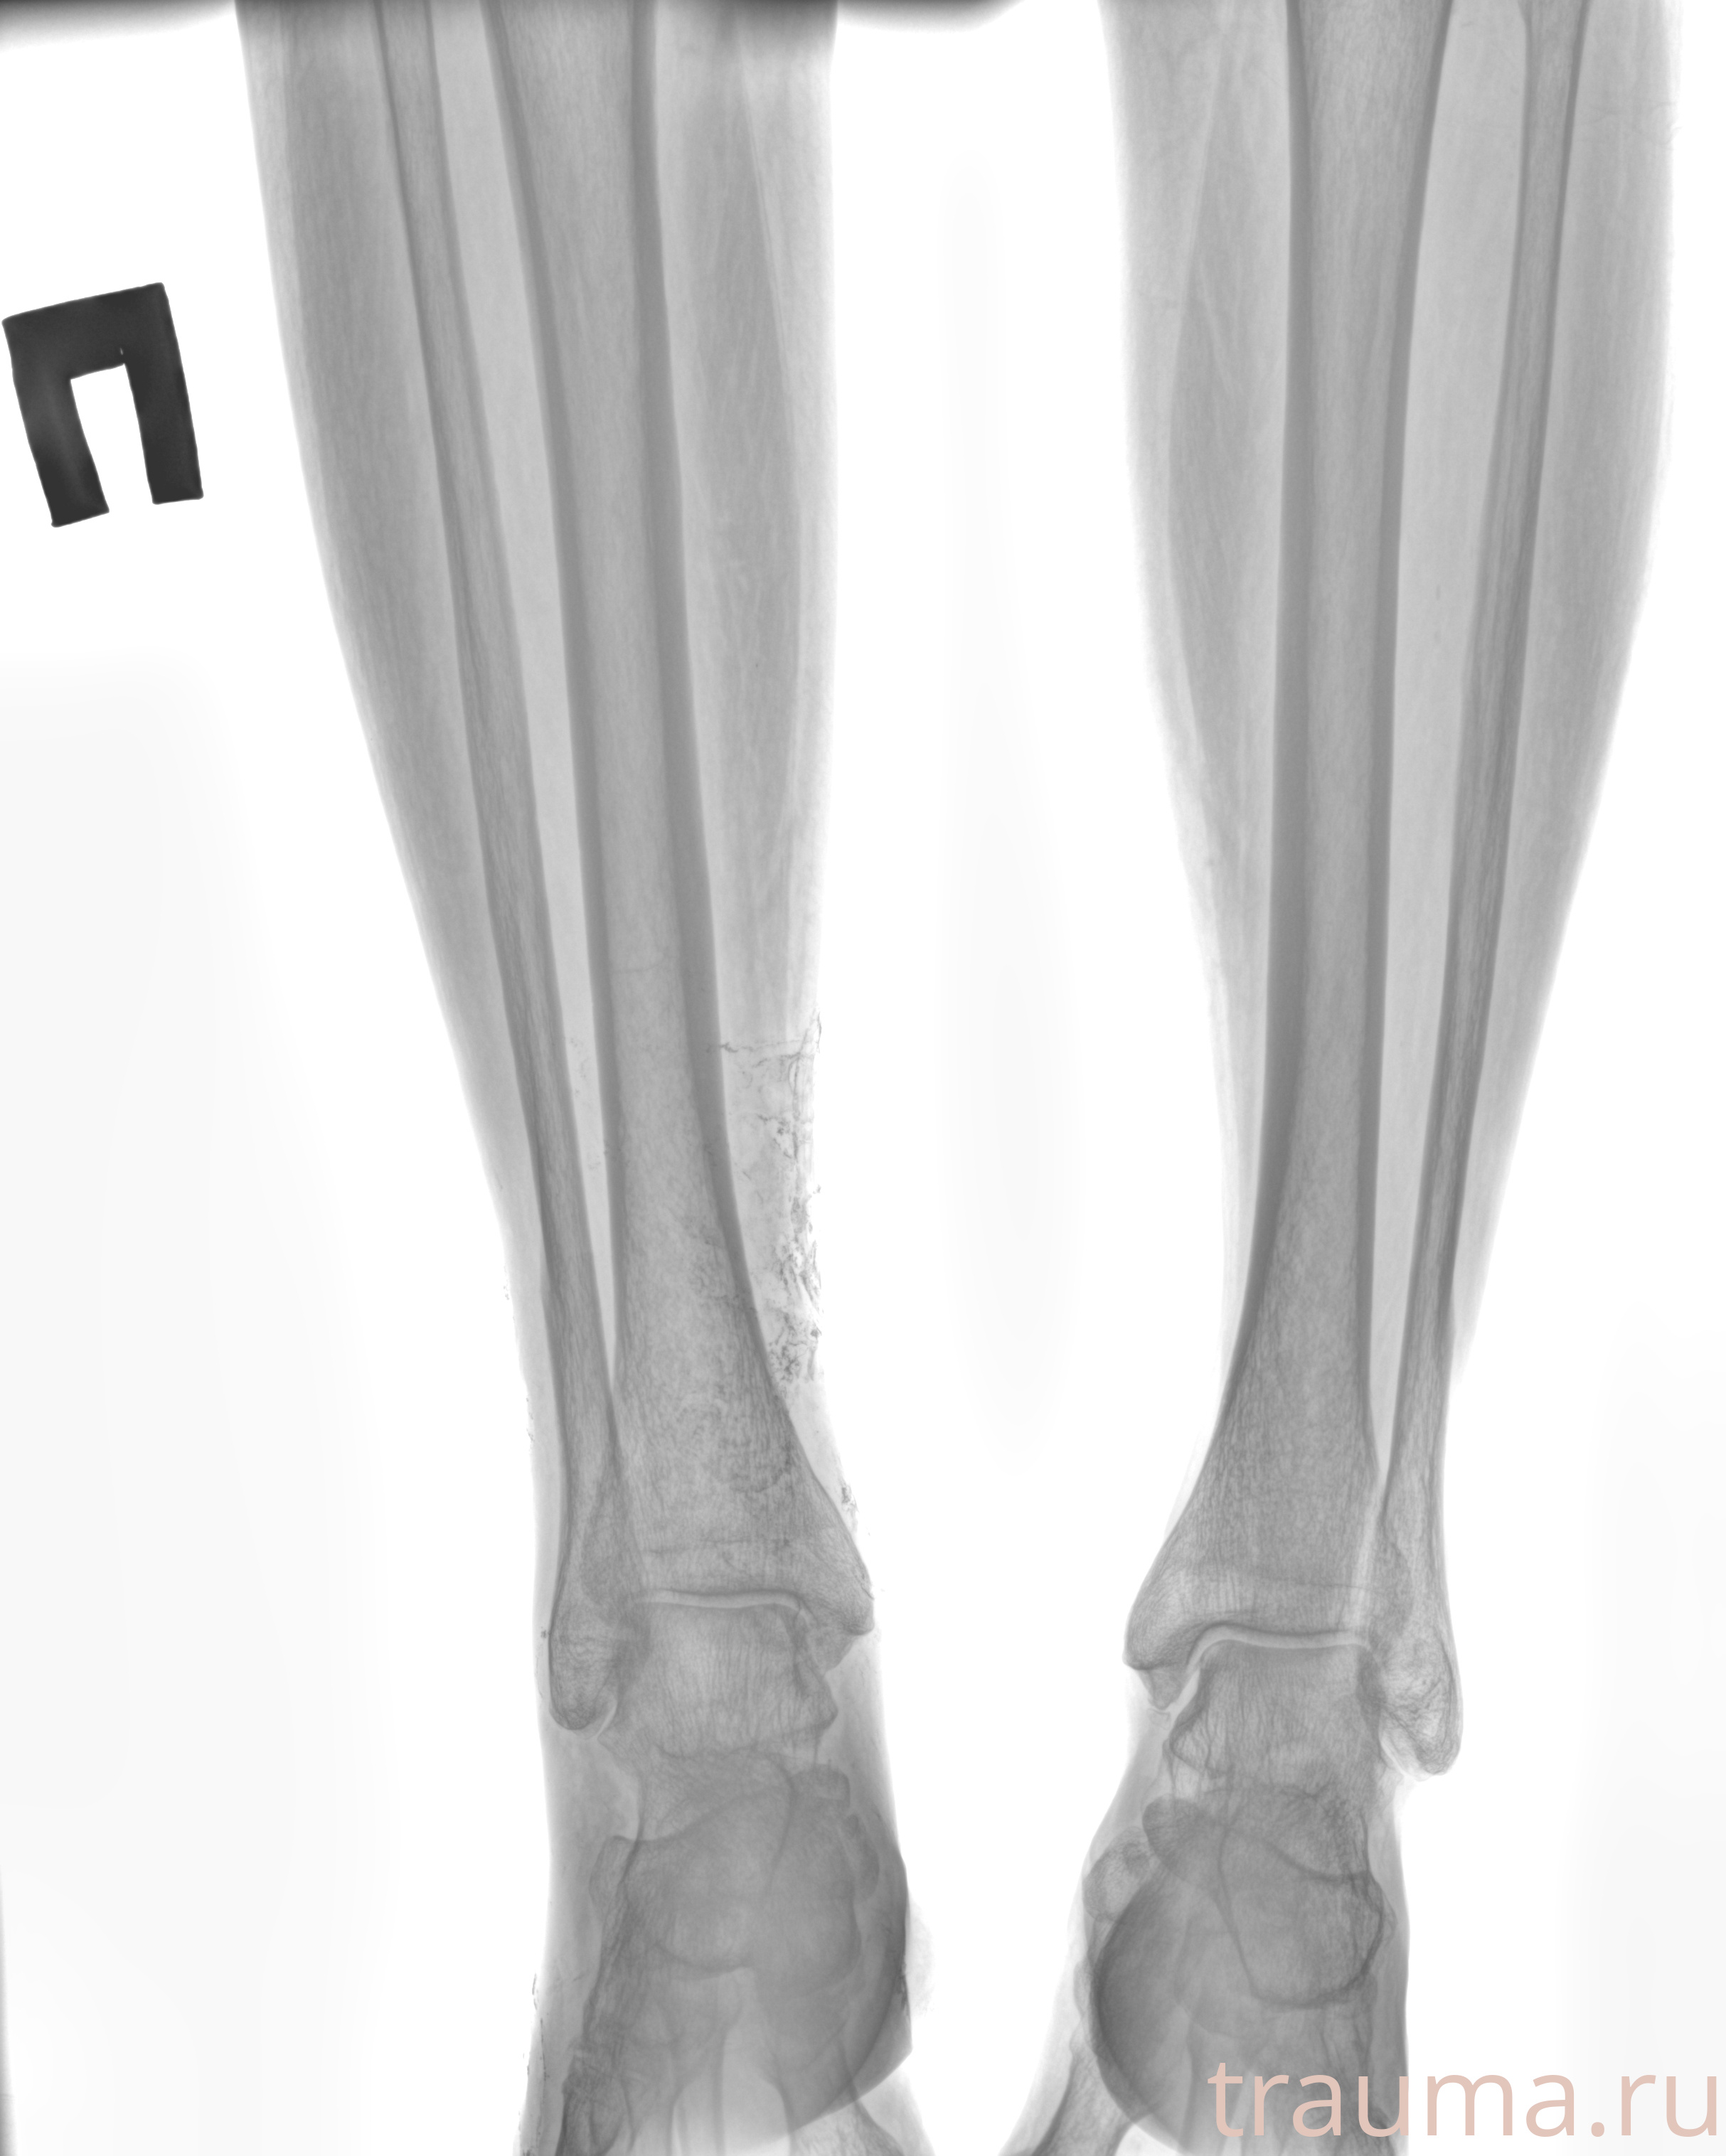

Рентгенограммы

Рентген на дому: по вашему адресу приезжает врач-рентгенолог, травматолог-ортопед с мобильным рентгеновским аппаратом, проводит диагностику травмы или заболевания, делает необходимые рентгенограммы, дает рекомендации по дальнейшему лечению. Получить качественные снимки в домашних условиях возможно благодаря уникальной методике, разработанной МосРентген Центром для института  Склифосовского